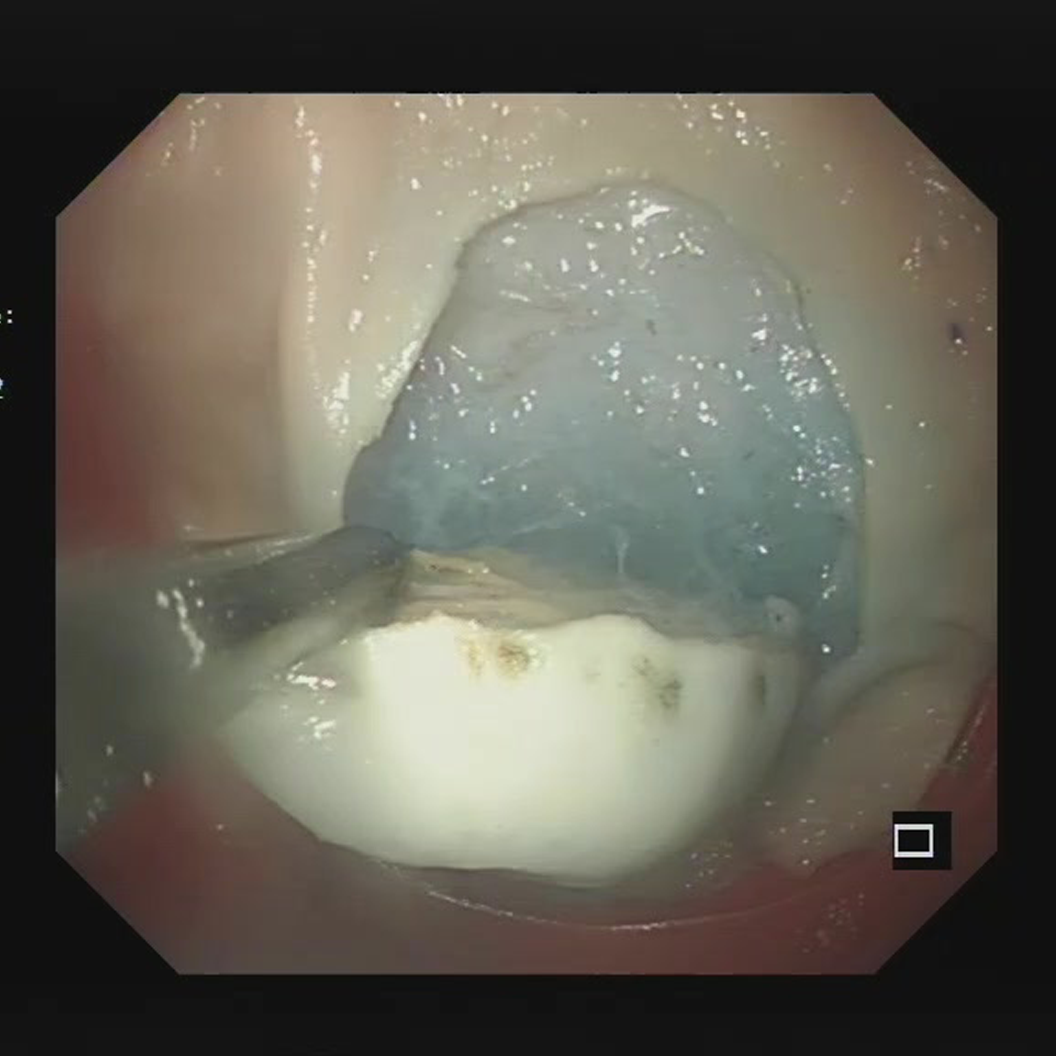

比如胃溃疡模型,在胃窦或者胃小弯的位置,能看到圆形的溃疡面,边缘整整齐齐,底部覆着白苔,周围的黏膜还有点轻微的充血水肿;

慢性胃炎模型呢,要么能看到浅表性胃炎的黏膜红斑、糜烂,要么能看出萎缩性胃炎的黏膜变薄、血管能透出来的样子;

胃癌模型更细致,能区分早期胃癌的小隆起、小凹陷,和进展期胃癌的肿块浸润、溃疡边缘不规整的形态。

这样一来,不用死记硬背病理描述,就能把“病变长什么样”和“到底是什么病”直接联系起来,记起来特别牢。